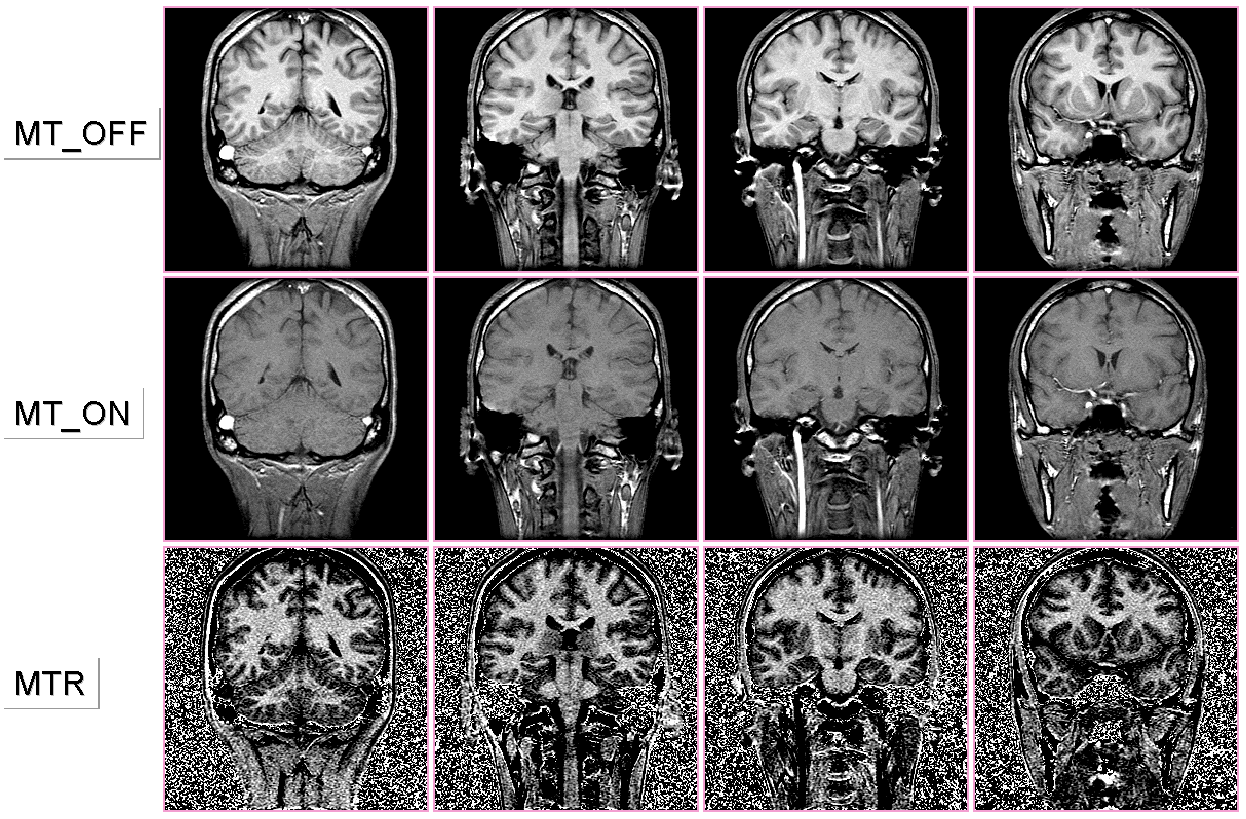

図8 上段:通常のT1強調画像、中段:MTパルス付加後のT1強調画像

下段:両者から算出したMTR画像

図8にMTR画像の例を示す。MTR画像は通常のT1強調画像に比して白質構造の描出能に優れ、また神経路描出も可能である。このような多段面のMTR画像群に対し、最大値投影法を適用することにより脳白質構造(特にミエリン密度の高い神経路)の描出が三次元的に可能になる(図9参照)。